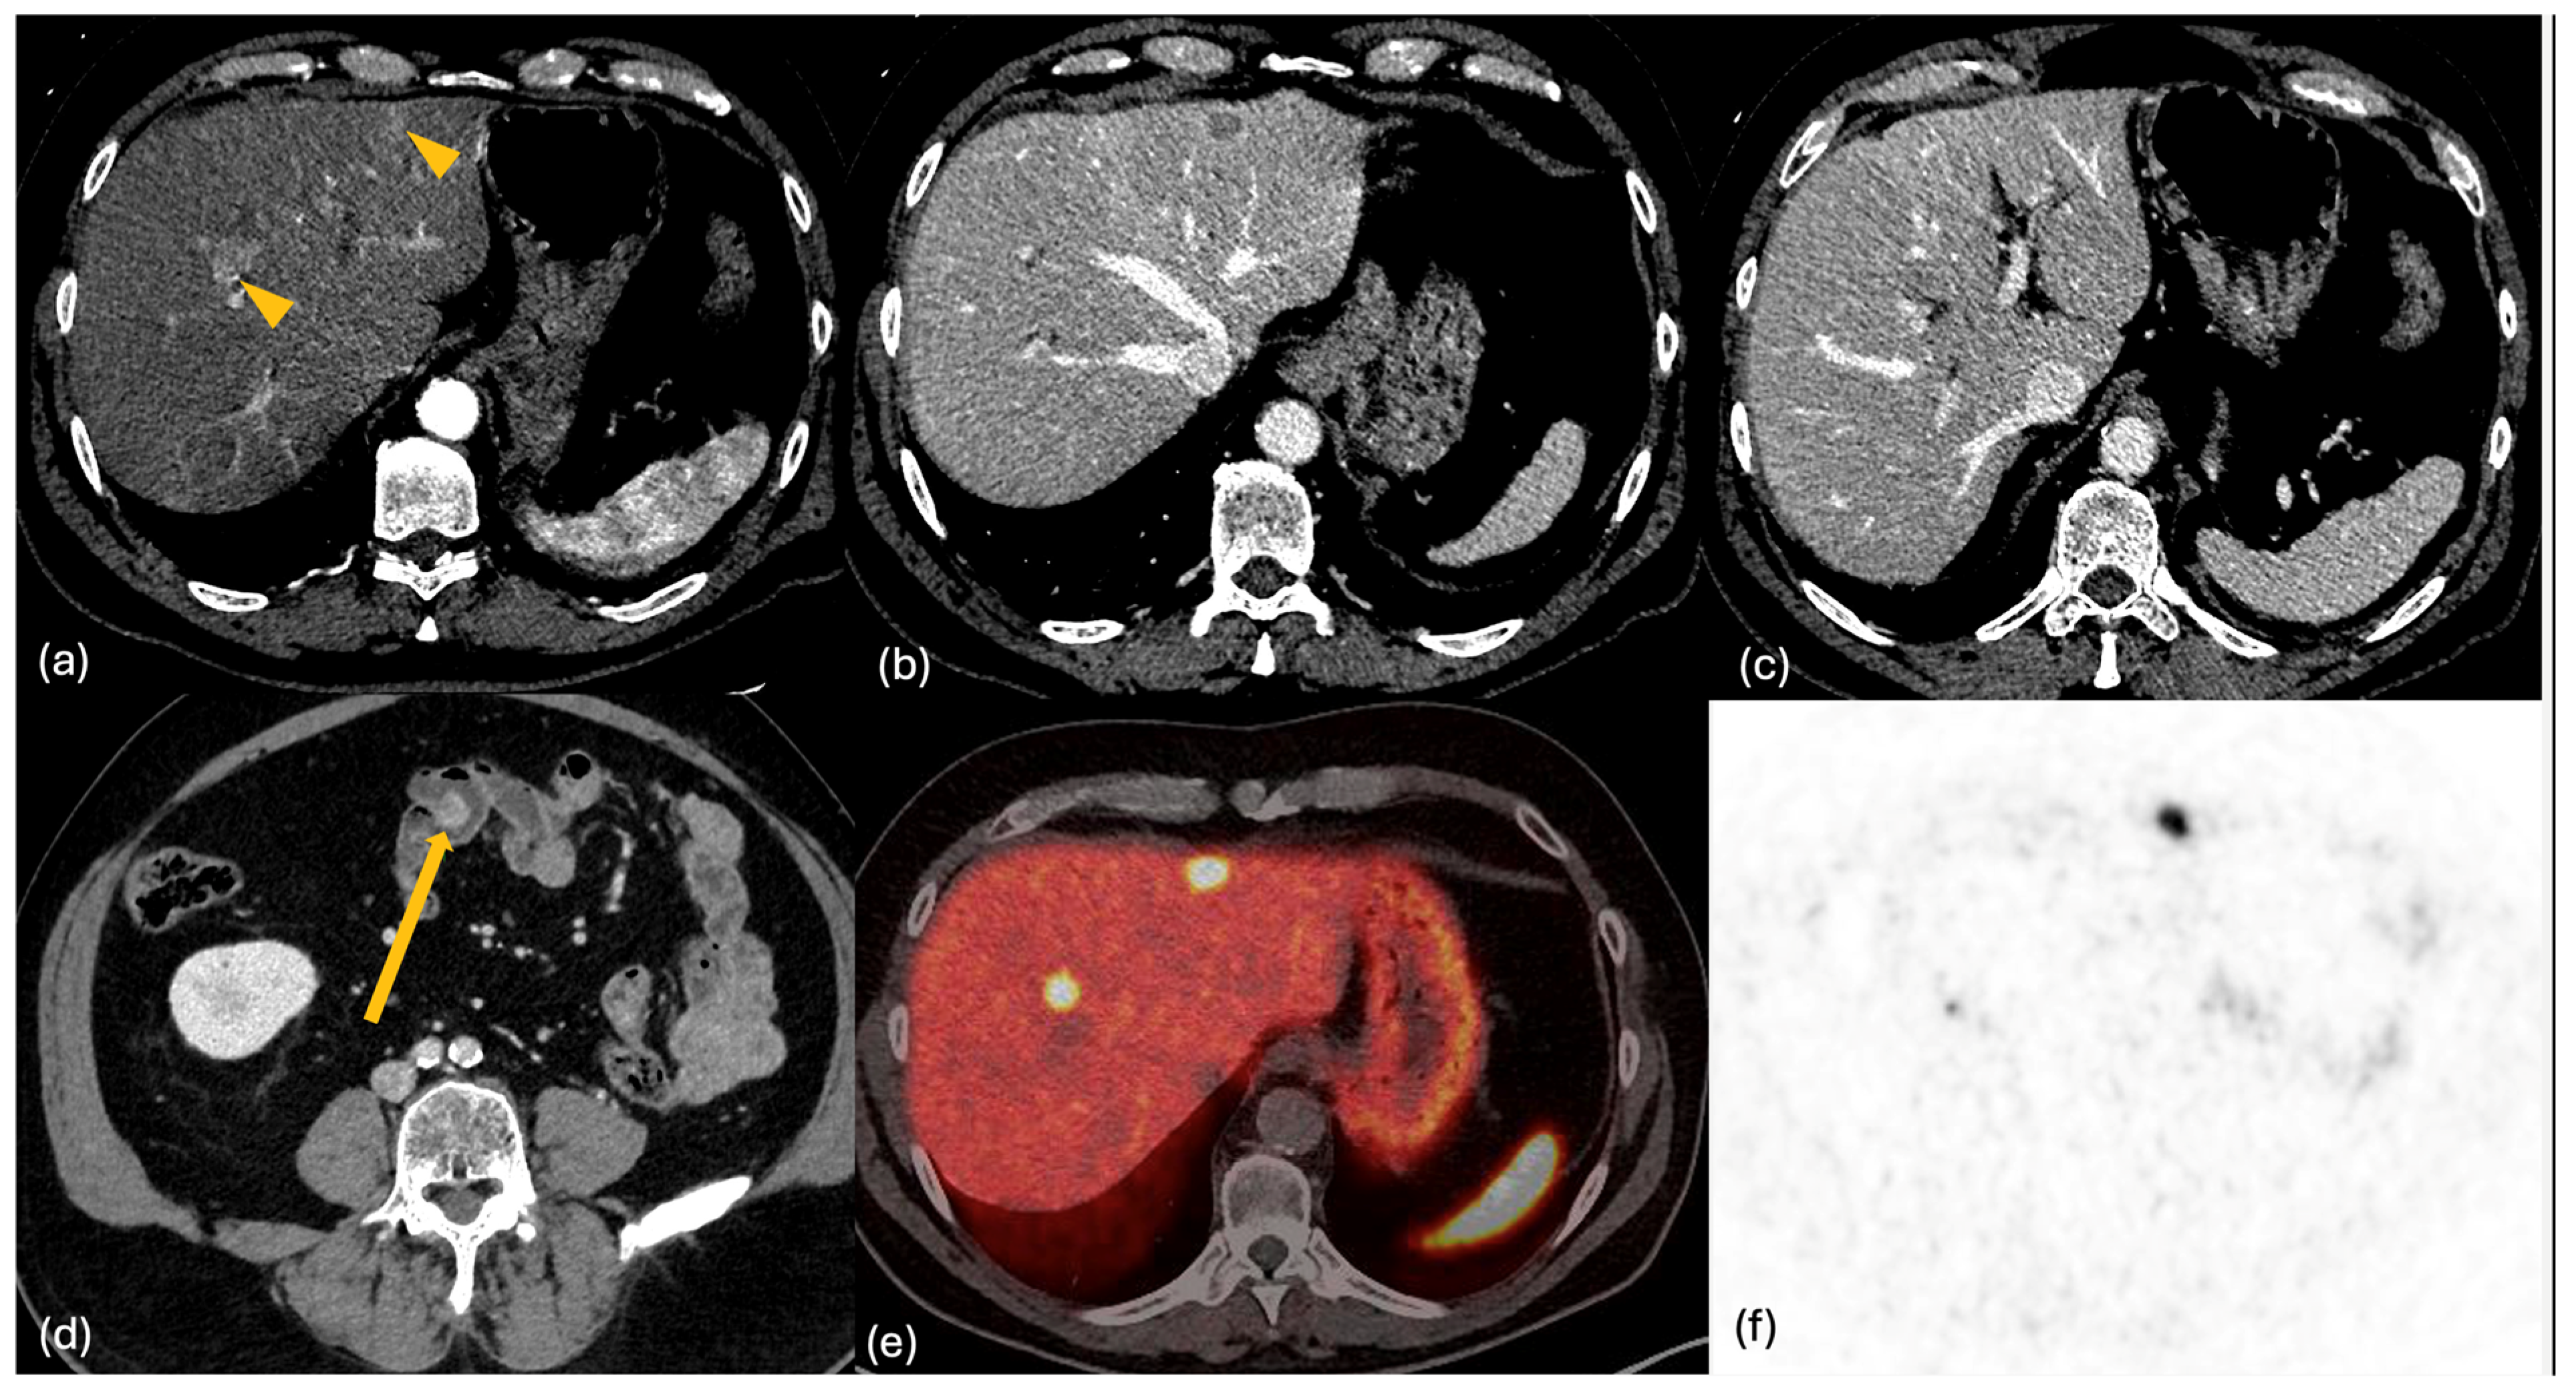

2.3. MRI

- Dromain, C.; de Baere, T.; Baudin, E.; Galline, J.; Ducreux, M.; Boige, V.; Duvillard, P.; Laplanche, A.; Caillet, H.; Lasser, P.; et al. MR imaging of hepatic metastases caused by neuroendocrine tumors: Comparing four techniques. AJR Am. J. Roentgenol. 2003, 180, 121–128. [Google Scholar] [CrossRef] [PubMed]

- Khanna, L.; Prasad, S.R.; Sunnapwar, A.; Kondapaneni, S.; Dasyam, A.; Tammisetti, V.S.; Salman, U.; Nazarullah, A.; Katabathina, V.S. Pancreatic Neuroendocrine Neoplasms: 2020 Update on Pathologic and Imaging Findings and Classification. Radiographics 2020, 40, 1240–1262. [Google Scholar] [CrossRef] [PubMed]

- Neri, E.; Bali, M.A.; Ba-Ssalamah, A.; Boraschi, P.; Brancatelli, G.; Alves, F.C.; Grazioli, L.; Helmberger, T.; Lee, J.M.; Manfredi, R.; et al. ESGAR consensus statement on liver MR imaging and clinical use of liver-specific contrast agents. Eur. Radiol. 2016, 26, 921–931. [Google Scholar] [CrossRef] [PubMed]

- Hayoz, R.; Vietti-Violi, N.; Duran, R.; Knebel, J.F.; Ledoux, J.B.; Dromain, C. The combination of hepatobiliary phase with Gd-EOB-DTPA and DWI is highly accurate for the detection and characterization of liver metastases from neuroendocrine tumor. Eur. Radiol. 2020, 30, 6593–6602. [Google Scholar] [CrossRef] [PubMed]

- Maino, C.; Vernuccio, F.; Cannella, R.; Cortese, F.; Franco, P.N.; Gaetani, C.; Giannini, V.; Inchingolo, R.; Ippolito, D.; Defeudis, A.; et al. Liver metastases: The role of magnetic resonance imaging. World J. Gastroenterol. 2023, 29, 5180–5197. [Google Scholar] [CrossRef] [PubMed]

- Karaosmanoglu, A.D.; Onur, M.R.; Ozmen, M.N.; Akata, D.; Karcaaltincaba, M. Magnetic Resonance Imaging of Liver Metastasis. Semin. Ultrasound CT MR 2016, 37, 533–548. [Google Scholar] [CrossRef] [PubMed]

- d’Assignies, G.; Fina, P.; Bruno, O.; Vullierme, M.P.; Tubach, F.; Paradis, V.; Sauvanet, A.; Ruszniewski, P.; Vilgrain, V. High sensitivity of diffusion-weighted MR imaging for the detection of liver metastases from neuroendocrine tumors: Comparison with T2-weighted and dynamic gadolinium-enhanced MR imaging. Radiology 2013, 268, 390–399. [Google Scholar] [CrossRef] [PubMed]

- Grazzini, G.; Danti, G.; Cozzi, D.; Lanzetta, M.M.; Addeo, G.; Falchini, M.; Masserelli, A.; Pradella, S.; Miele, V. Diagnostic imaging of gastrointestinal neuroendocrine tumours (GI-NETs): Relationship between MDCT features and 2010 WHO classification. Radiol. Med. 2019, 124, 94–102. [Google Scholar] [CrossRef] [PubMed]

2.4. PET-CT

- Fabritius, M.P.; Soltani, V.; Cyran, C.C.; Ricke, J.; Bartenstein, P.; Auernhammer, C.J.; Spitzweg, C.; Schnitzer, M.L.; Ebner, R.; Mansournia, S.; et al. Diagnostic accuracy of SSR-PET/CT compared to histopathology in the identification of liver metastases from well-differentiated neuroendocrine tumors. Cancer Imaging 2023, 23, 92. [Google Scholar] [CrossRef] [PubMed]

- Kayani, I.; Bomanji, J.B.; Groves, A.; Conway, G.; Gacinovic, S.; Win, T.; Dickson, J.; Caplin, M.; Ell, P.J. Functional imaging of neuroendocrine tumors with combined PET/CT using 68Ga-DOTATATE (DOTA-DPhe1, Tyr3-octreotate) and 18F-FDG. Cancer 2008, 112, 2447–2455. [Google Scholar] [CrossRef] [PubMed]

- Binderup, T.; Knigge, U.; Loft, A.; Federspiel, B.; Kjaer, A. 18F-fluorodeoxyglucose positron emission tomography predicts survival of patients with neuroendocrine tumors. Clin. Cancer Res. 2010, 16, 978–985. [Google Scholar] [CrossRef] [PubMed]